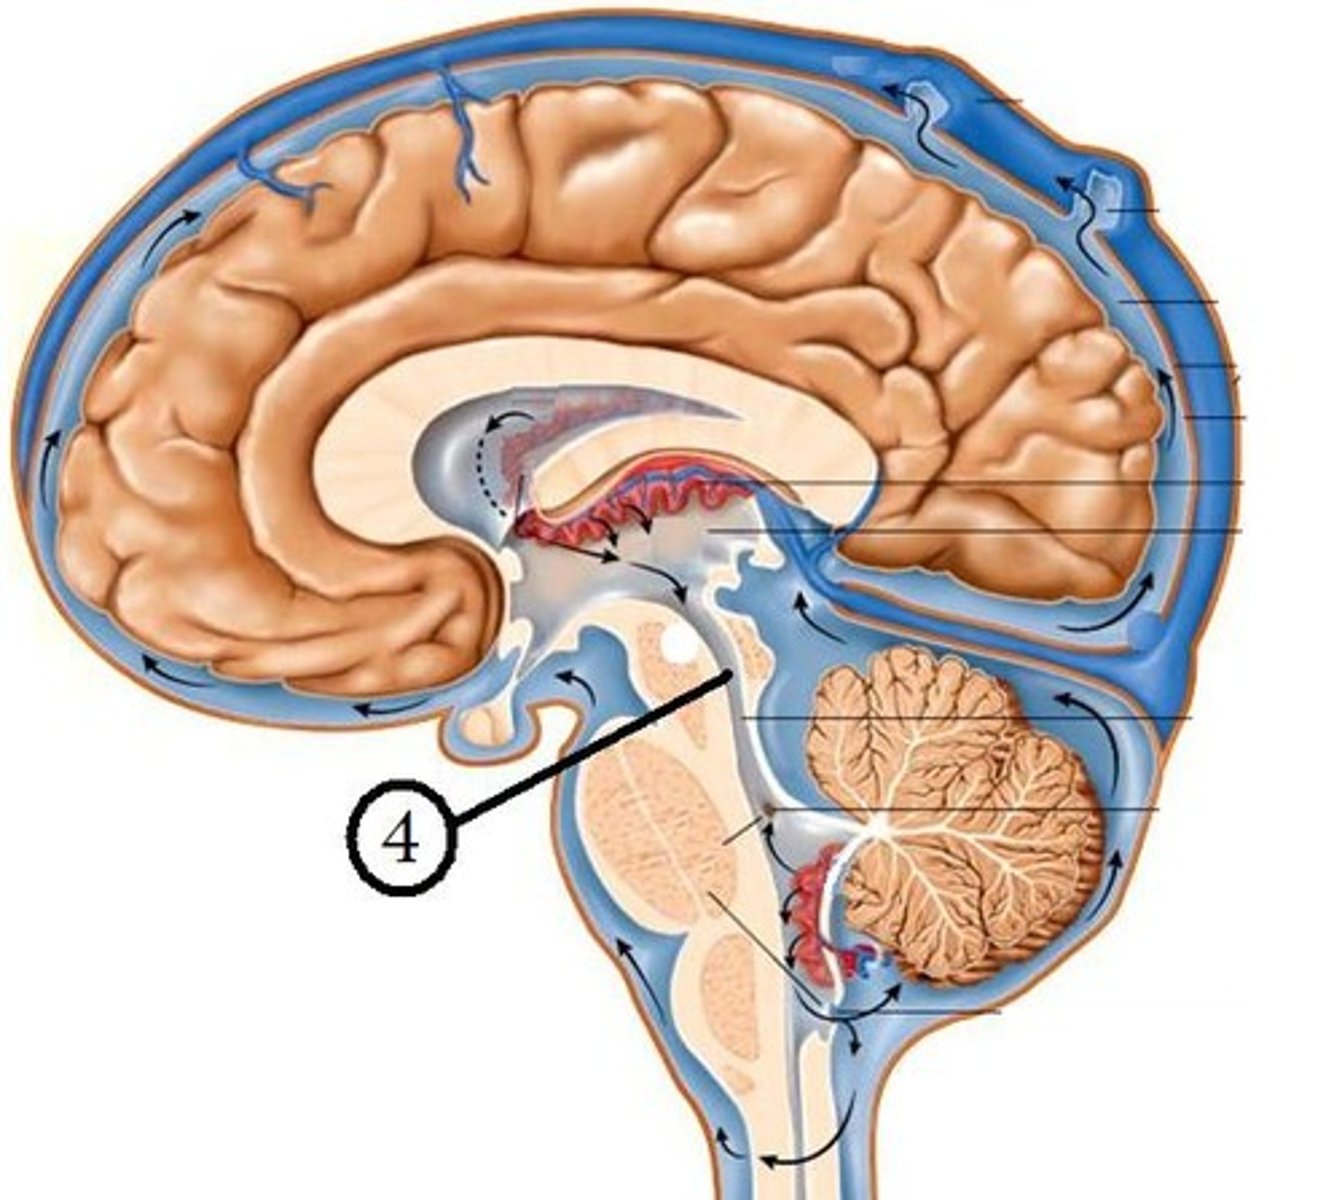

CSF circualtion

flows out of the ventricular system by the medial foramen of Magendie or two lateral foramina of Lushka into subarachnoid space and central canal

In subarachnoid space, CSF circulates until what?

it reaches arachnoid granulations that protrude into superior sagittal venous sinus

How is CSF reabsorbed?

arachnoid granulations/villi

Arachnoid granulations

Extensions of the arachnoid mater that allow excess CSF to be absorbed by the dural sinuses